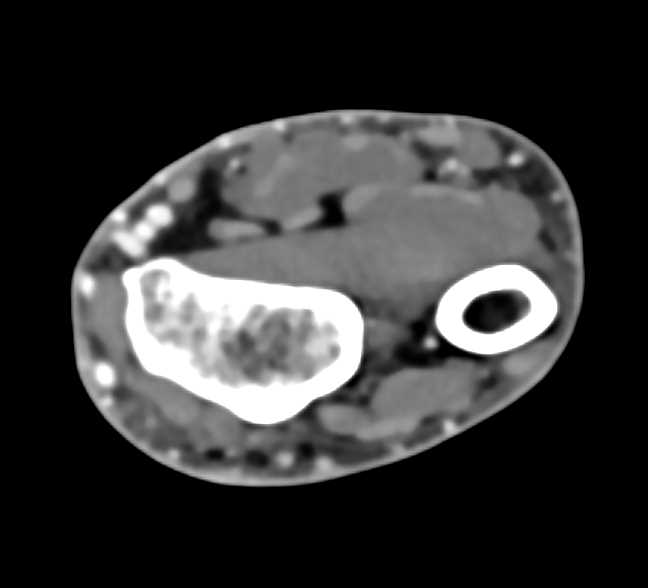

Abscess with Cellulitis in the Forearm – Musculoskeletal Case Studies …

Abscess with Cellulitis in the Forearm – Musculoskeletal Case Studies …

Abscess with Cellulitis in the Forearm – Musculoskeletal Case Studies …

IVDA with Abscess in Arm and Poor Function Left Kidney …

IVDA with Abscess in Arm and Poor Function Left Kidney …